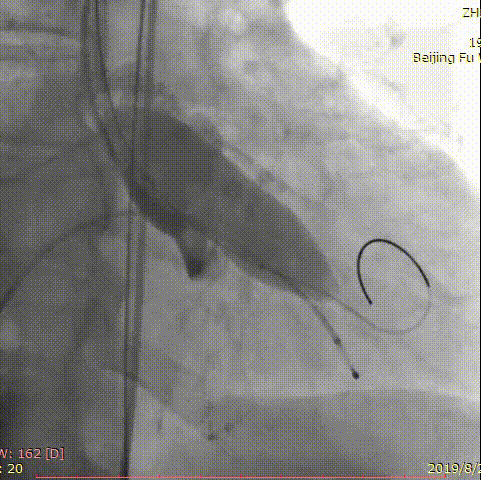

第三位患者是一位84岁女性,因间断头晕伴气短2年,加重1年入院,超声心动图提示主动脉瓣重度狭窄,左室壁肥厚,节段性室壁运动减低,主动脉瓣平均跨瓣压差91mmHg,收缩期流速 m/s,瓣口面积 0.6cm2。患者合并房颤、慢性肾功能不全、贫血。完善CT检查,测得主动脉瓣环 21*25mm,周长71.3mm,面积399.2mm2,患者三叶瓣,钙化分布较均匀,结合瓣上多平面分析方法,选择经左侧股动脉,应用微创心通 20*40mm敖广球囊预扩张,并成功植入Vitaflow 24mm主动脉瓣膜。术后超声提示收缩期流速1.7m/s,较术前明显下降。

术前影像